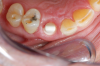

Fig 1. Preoperative surgery.

Figure 1